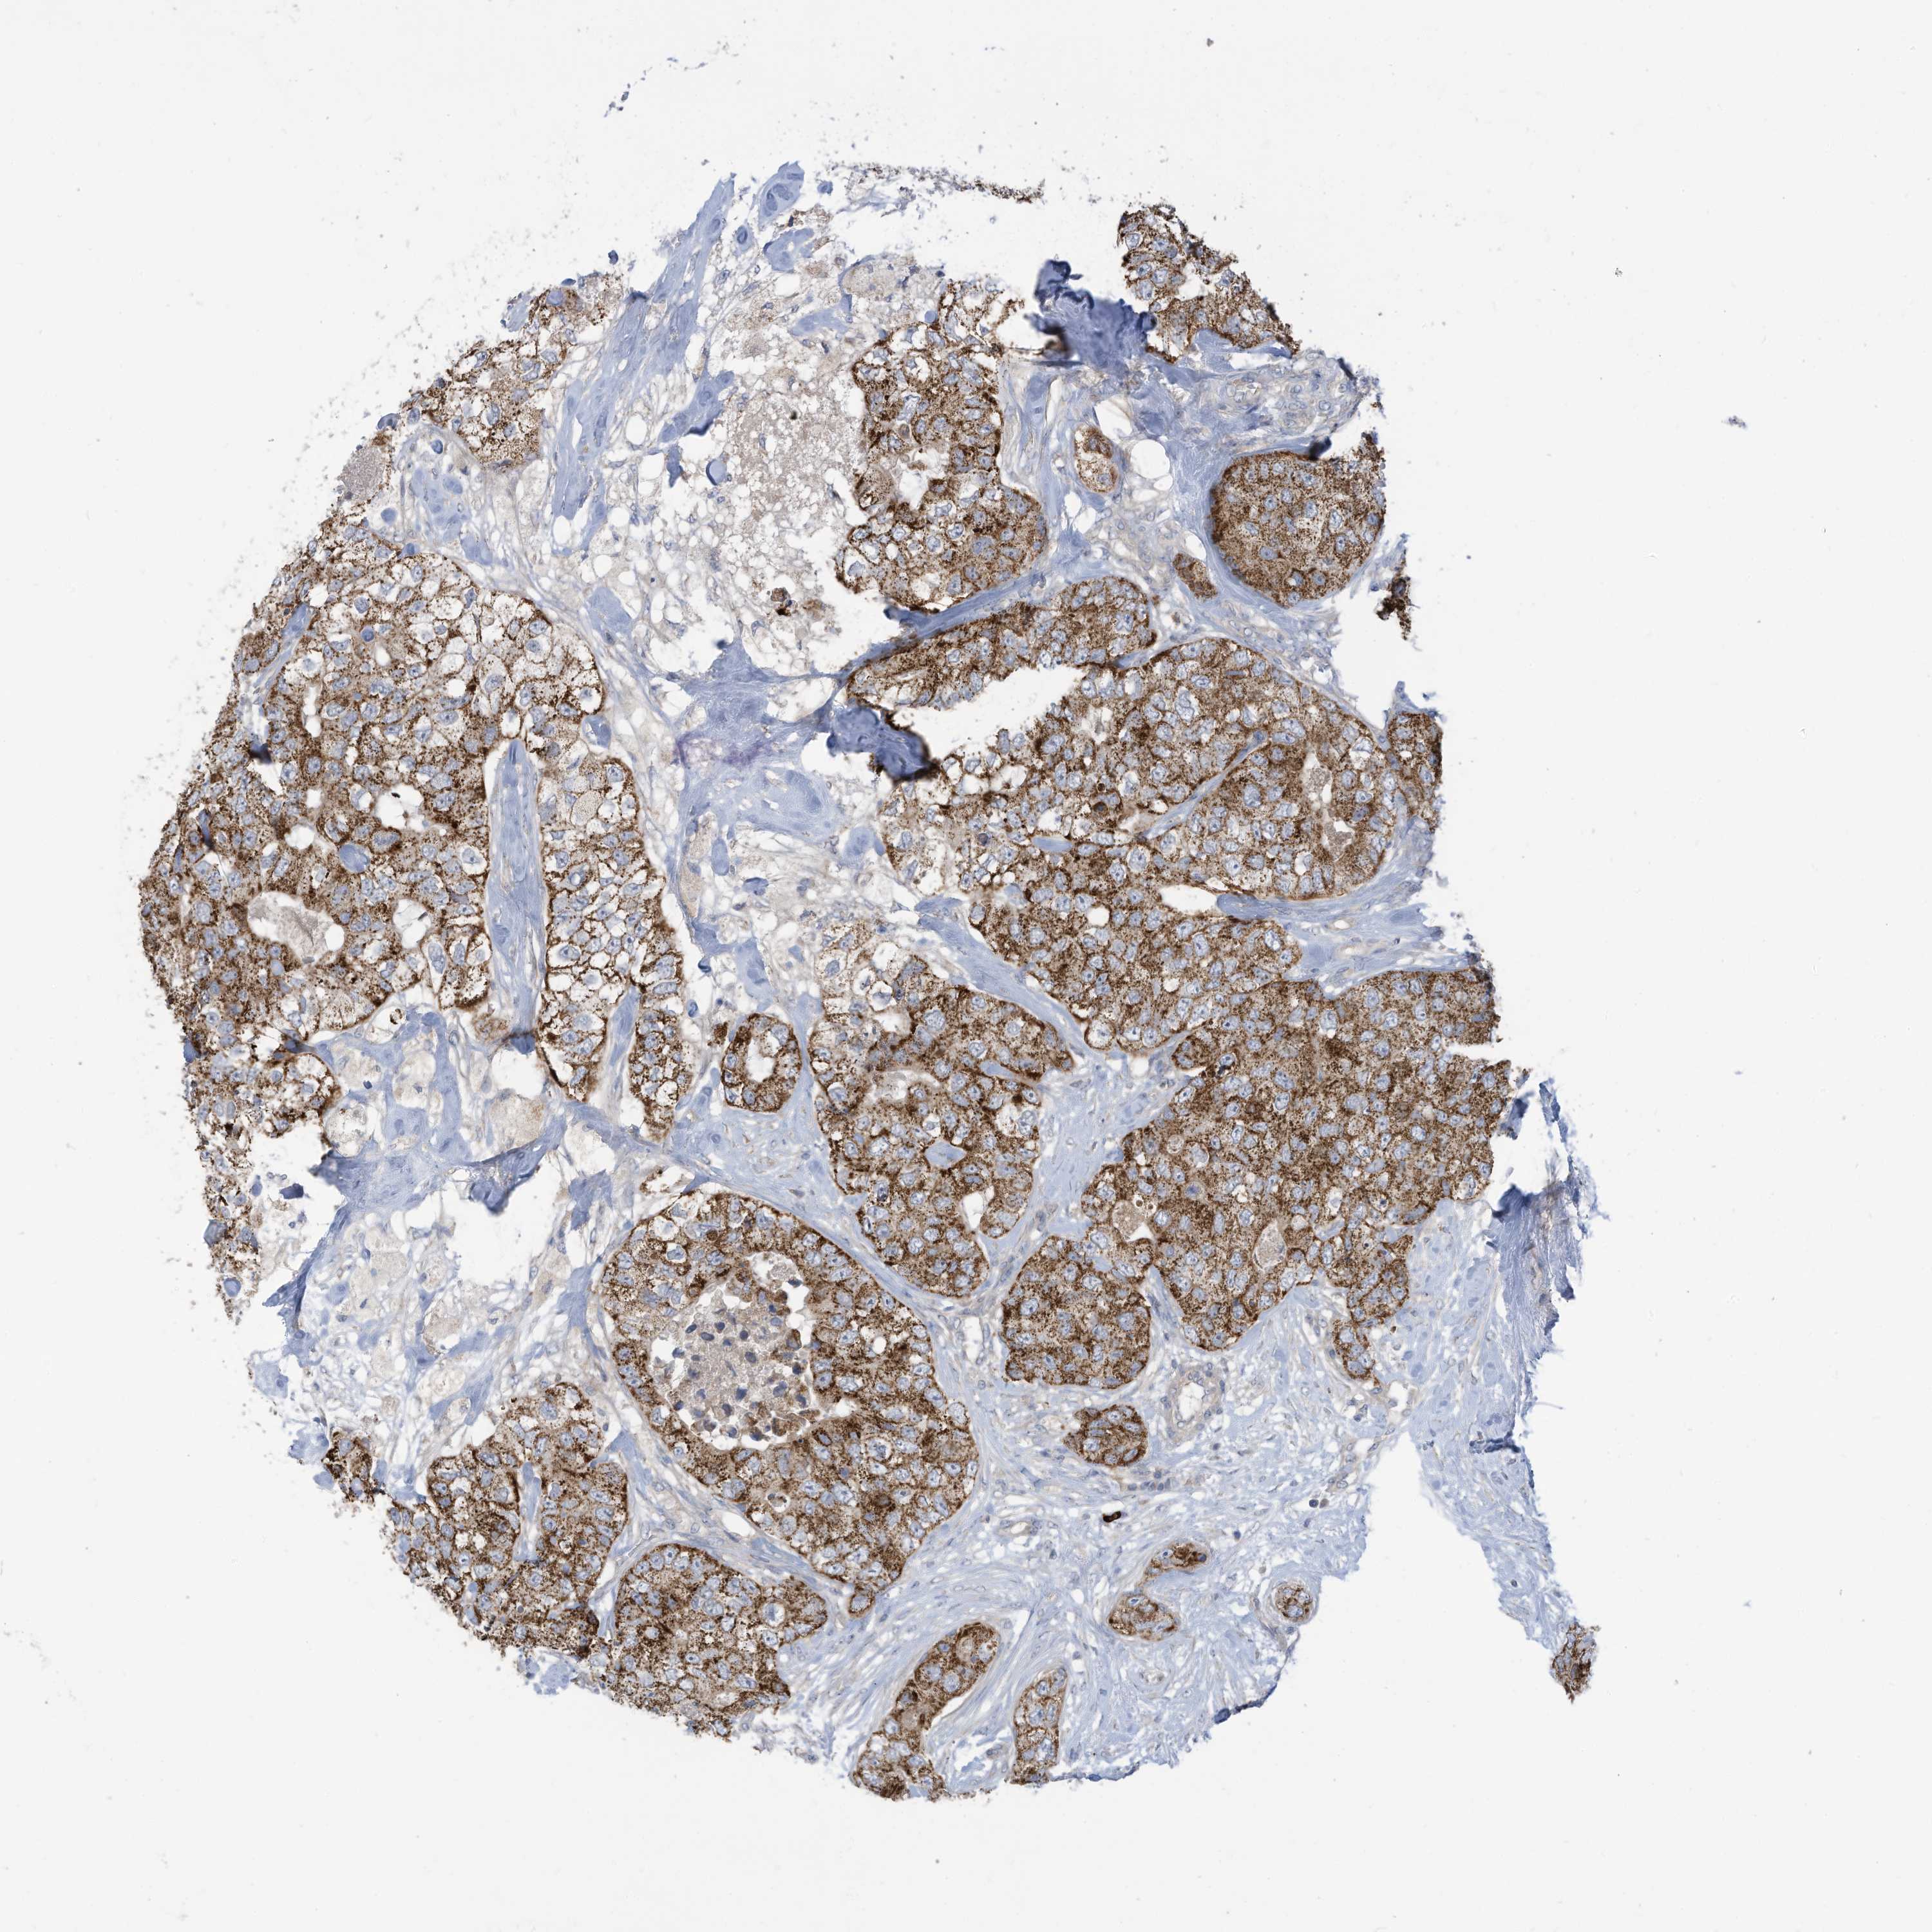

CANCER BREAST CANCER Show tissue menu

BRCA TCGA BRCA VALIDATION PROTEIN EXPRESSION